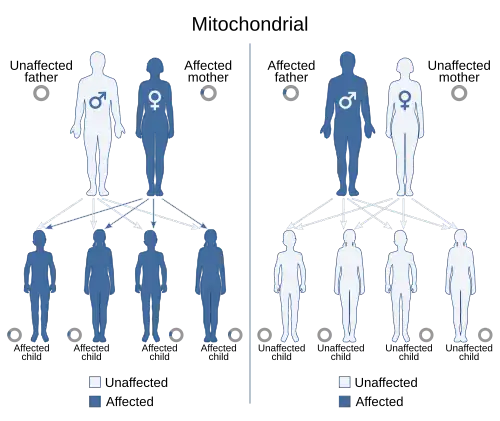

- Mitochondrial inheritance: This pattern affects both males and females but is inherited and passed only through the mother.[24] Examples include Leber’s hereditary optic neuropathy and Kearns-Sayre syndrome. [24]